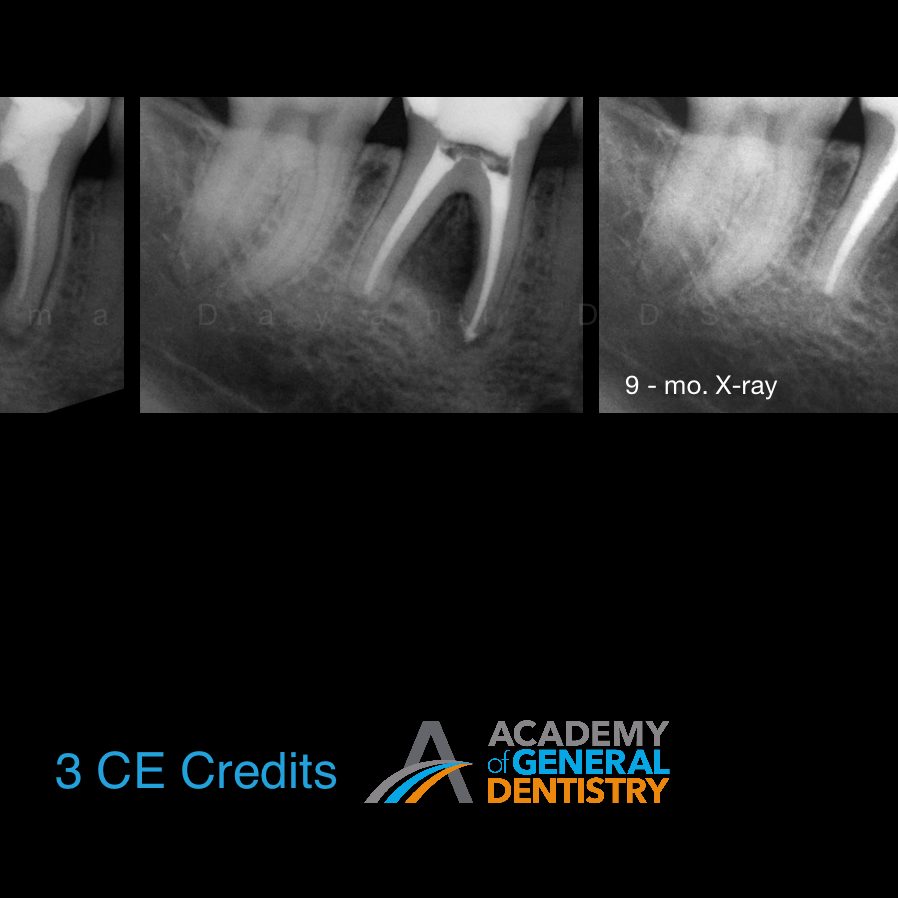

From www.semanticscholar.org

Figure 2 from Management of Endodontic Failure Semantic Scholar Failed Endodontic Treatment This case series provided further evidence for the possible causes for the failure of endodontic surgery, aiding clinicians in their preparation. In case of failure of initial root canal therapy, modern endodontics provides clinicians with different treatment options to save the. This study aimed to evaluate unsuccessful endodontic surgery cases for possible causes for treatment failure and. Failed endodontic treatment. Failed Endodontic Treatment.

From www.researchgate.net

Successful surgery with failed endodontic retreatment. Preoperative Failed Endodontic Treatment This study aimed to evaluate unsuccessful endodontic surgery cases for possible causes for treatment failure and. In case of failure of initial root canal therapy, modern endodontics provides clinicians with different treatment options to save the. Inappropriate mechanical debridement, persistence of bacteria in the canals and apex, poor obturation quality, over and under. Clinical and radiographic control (preservation) is extremely.. Failed Endodontic Treatment.

Typical failure case of endodontic surgery. a Preoperative radiograph Failed Endodontic Treatment Inappropriate mechanical debridement, persistence of bacteria in the canals and apex, poor obturation quality, over and under. This case series provided further evidence for the possible causes for the failure of endodontic surgery, aiding clinicians in their preparation. If nonsurgical retreatment is not an option, then endodontic surgery should be considered. This surgery involves making an incision to allow. While. Failed Endodontic Treatment.